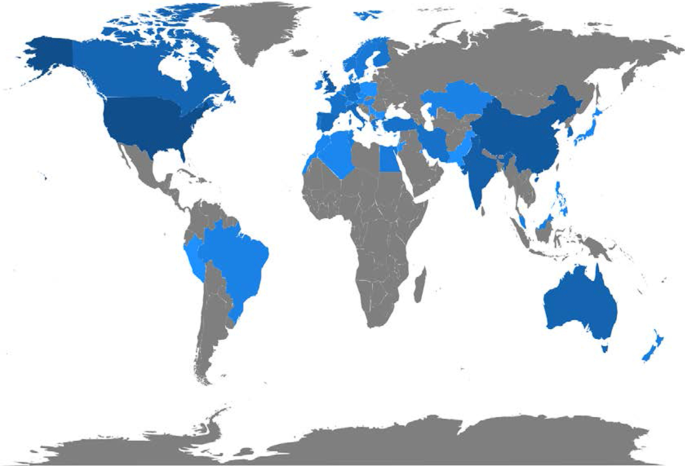

The investigation showed that the literature in this field is emerging. It focuses on health services management, predictive medicine, patient data and diagnostics, and clinical decision-making. The United States, China, and the United Kingdom contributed the highest number of studies. Keyword analysis revealed that AI can support physicians in making a diagnosis, predicting the spread of diseases and customising treatment paths.

A topic dendrogram study that identifies five research clusters: health services management, predictive medicine, patient data, diagnostics, and finally, clinical decision-making.